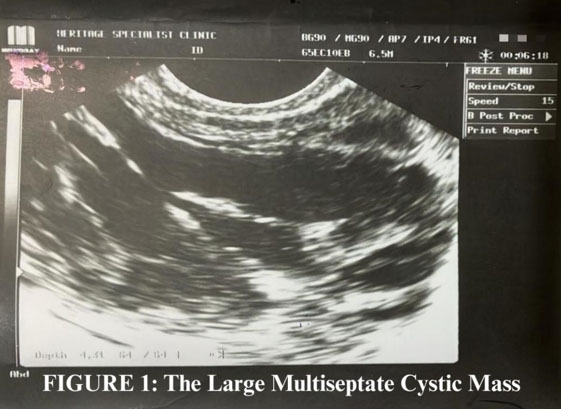

Case Report: A 31-year-old primigravida with a history of polycystic ovary syndrome (PCOS), obesity, and anemia conceived dichorionic-diamniotic twins with clomiphene. The patient had spontaneous early loss of Twin A at about eight weeks’ gestation, which was confirmed by ultrasound as vanishing twin syndrome. The surviving fetus (Twin B) demonstrated appropriate developmental growth and was large-for-gestational-age (LGA) through 33 weeks. At 34+4 weeks, the patient presented with decreased fetal movement, and IUFD was confirmed. Placental pathology and fetal karyotype were unremarkable, despite grossly abnormal placental architecture upon delivery. Two months postpartum, thrombophilia testing revealed a methylenetetrahydrofolate reductase (MTHFR) mutation, low protein S activity, and low PT/INR, highlighting the possibility of a subclinical thrombotic or microvascular process leading up to the fatal event.